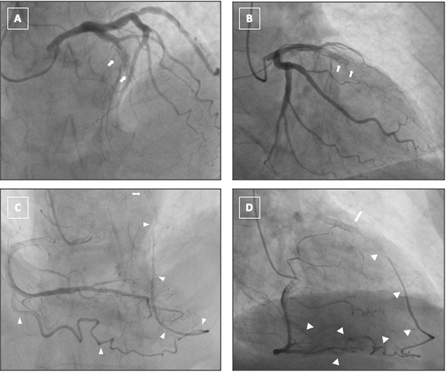

Video 1. Left coronary angiography in a left coronary artery right anterior oblique 24°/cranial 3° projection showed an in-stent chronic total occlusion of the mid-left anterior descending artery with no distal opacification.

Video 2. Complementary left coronary angiography in left anterior oblique 4°/cranial 35° projection confirmed mid-left anterior descending artery in-stent chronic total occlusion with absent antegrade distal flow.

Video 3. Right coronary angiography in left anterior oblique 6°/cranial 24° projection showed a single epicardial collateral arising from the acute marginal branch and supplying the distal left anterior descending artery.

Video 4. Right coronary artery-acute marginal epicardial collateral to the left anterior descending artery, right anterior oblique 38°/cranial 13°.

Video 5. Balloon occlusion of the acute marginal branch demonstrated in LAO 25°/CRAN 6° projection showed complete interruption of epicardial collateral flow without recruitment of additional channels.

Video 6. Balloon occlusion of the acute marginal branch demonstrated in RAO 28°/CRAN 34°projection showed complete interruption of epicardial collateral flow without recruitment of additional channels.